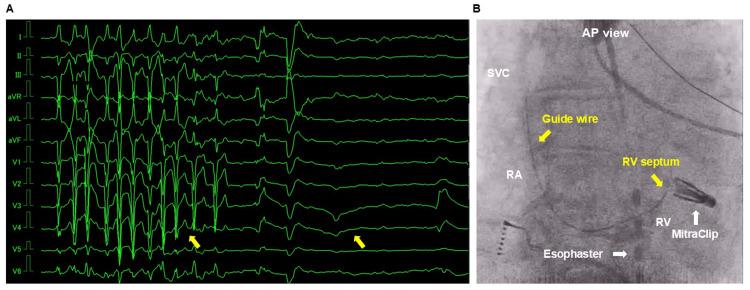

Right bundle branch block can occasionally occur when a guide wire or catheter is inserted into the heart. An 83-year-old woman with preexisting left bundle branch block (LBBB) was diagnosed with paroxysmal atrial fibrillation (PAF) and severe mitral regurgitation (MR). The patient was started on amiodarone (100 mg/day) and bisoprolol (1.25 mg/day). The patient underwent catheter ablation for PAF after a percutaneous edge-to-edge mitral valve repair for MR. During the ablation procedure, performed under a sedation with dexmedetomidine, guide wire stimulation led to a paroxysmal atrioventricular block (AVB), resulting in cardiac arrest. Cardiopulmonary resuscitation was performed for 2 min, one ampule of intravenous adrenaline was administered, and a return of spontaneous circulation was obtained. The patient subsequently developed takotsubo cardiomyopathy due to the administration of catecholamines. Three months later, re-ablation was performed safely under fluoroscopic guidance and the use of noninvasive transcutaneous pacemaker. Fluoroscopic guide wire manipulation and the use of noninvasive transcutaneous pacemaker are essential for patients with LBBB to prevent paroxysmal AVB and cardiac arrest.

当导丝或导管插入心脏时,偶尔会发生右束支传导阻滞。一名患有左束支传导阻滞(LBBB)的83岁女性被诊断为阵发性心房颤动(PAF)和严重二尖瓣反流(MR)。患者开始服用胺碘酮(100毫克/天)和比索洛尔(1.25毫克/天)。在经皮二尖瓣缘对缘修复治疗MR后,患者接受了PAF的导管消融术。在使用右美托咪定镇静的情况下进行消融手术时,导丝刺激导致阵发性房室传导阻滞(AVB),进而引发心脏骤停。进行了2分钟的心肺复苏,静脉注射了一剂肾上腺素,恢复了自主循环。患者随后因使用儿茶酚胺而发生应激性心肌病。三个月后,在荧光透视引导下并使用无创经皮起搏器安全地进行了再次消融。对于LBBB患者,荧光透视下导丝操作和使用无创经皮起搏器对于预防阵发性AVB和心脏骤停至关重要。